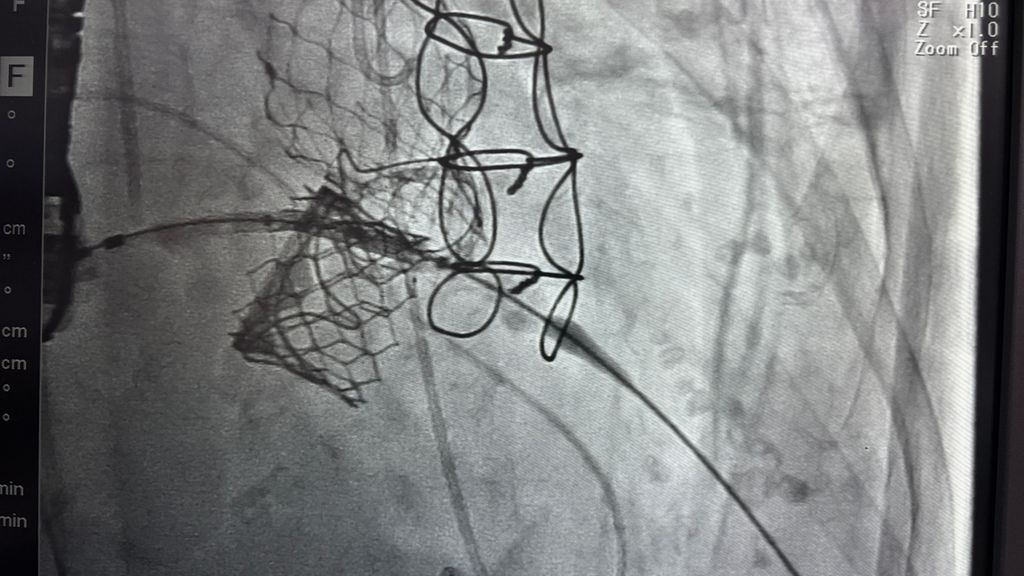

活豬解剖裝 Centrimag

一天兩台open heart真的會死人